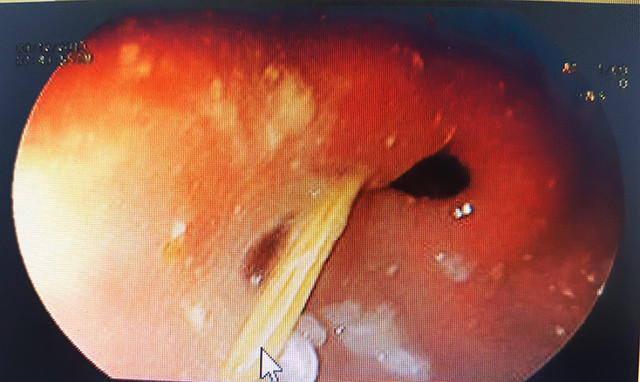

| Chiếc tăm nhọn đâm thủng dạ dày bệnh nhân |

Các bác sĩ Khoa Thăm dò chức năng nội soi của bệnh viện đã nội soi và gắp thành công chiếc tăm tre nhọn 2 đầu, dài khoảng 2cm, đâm thủng dạ dày mà không gây biến chứng chảy máu cho nam thanh niên.

Các bác sĩ cho biết chiếc tăm đã đâm xuyên hơn 1/3 vào thành dạ dày bệnh nhân, nếu phát hiện muộn chiếc tăm có thể làm thủng ruột non và các tạng lân cận rất nguy hiểm.